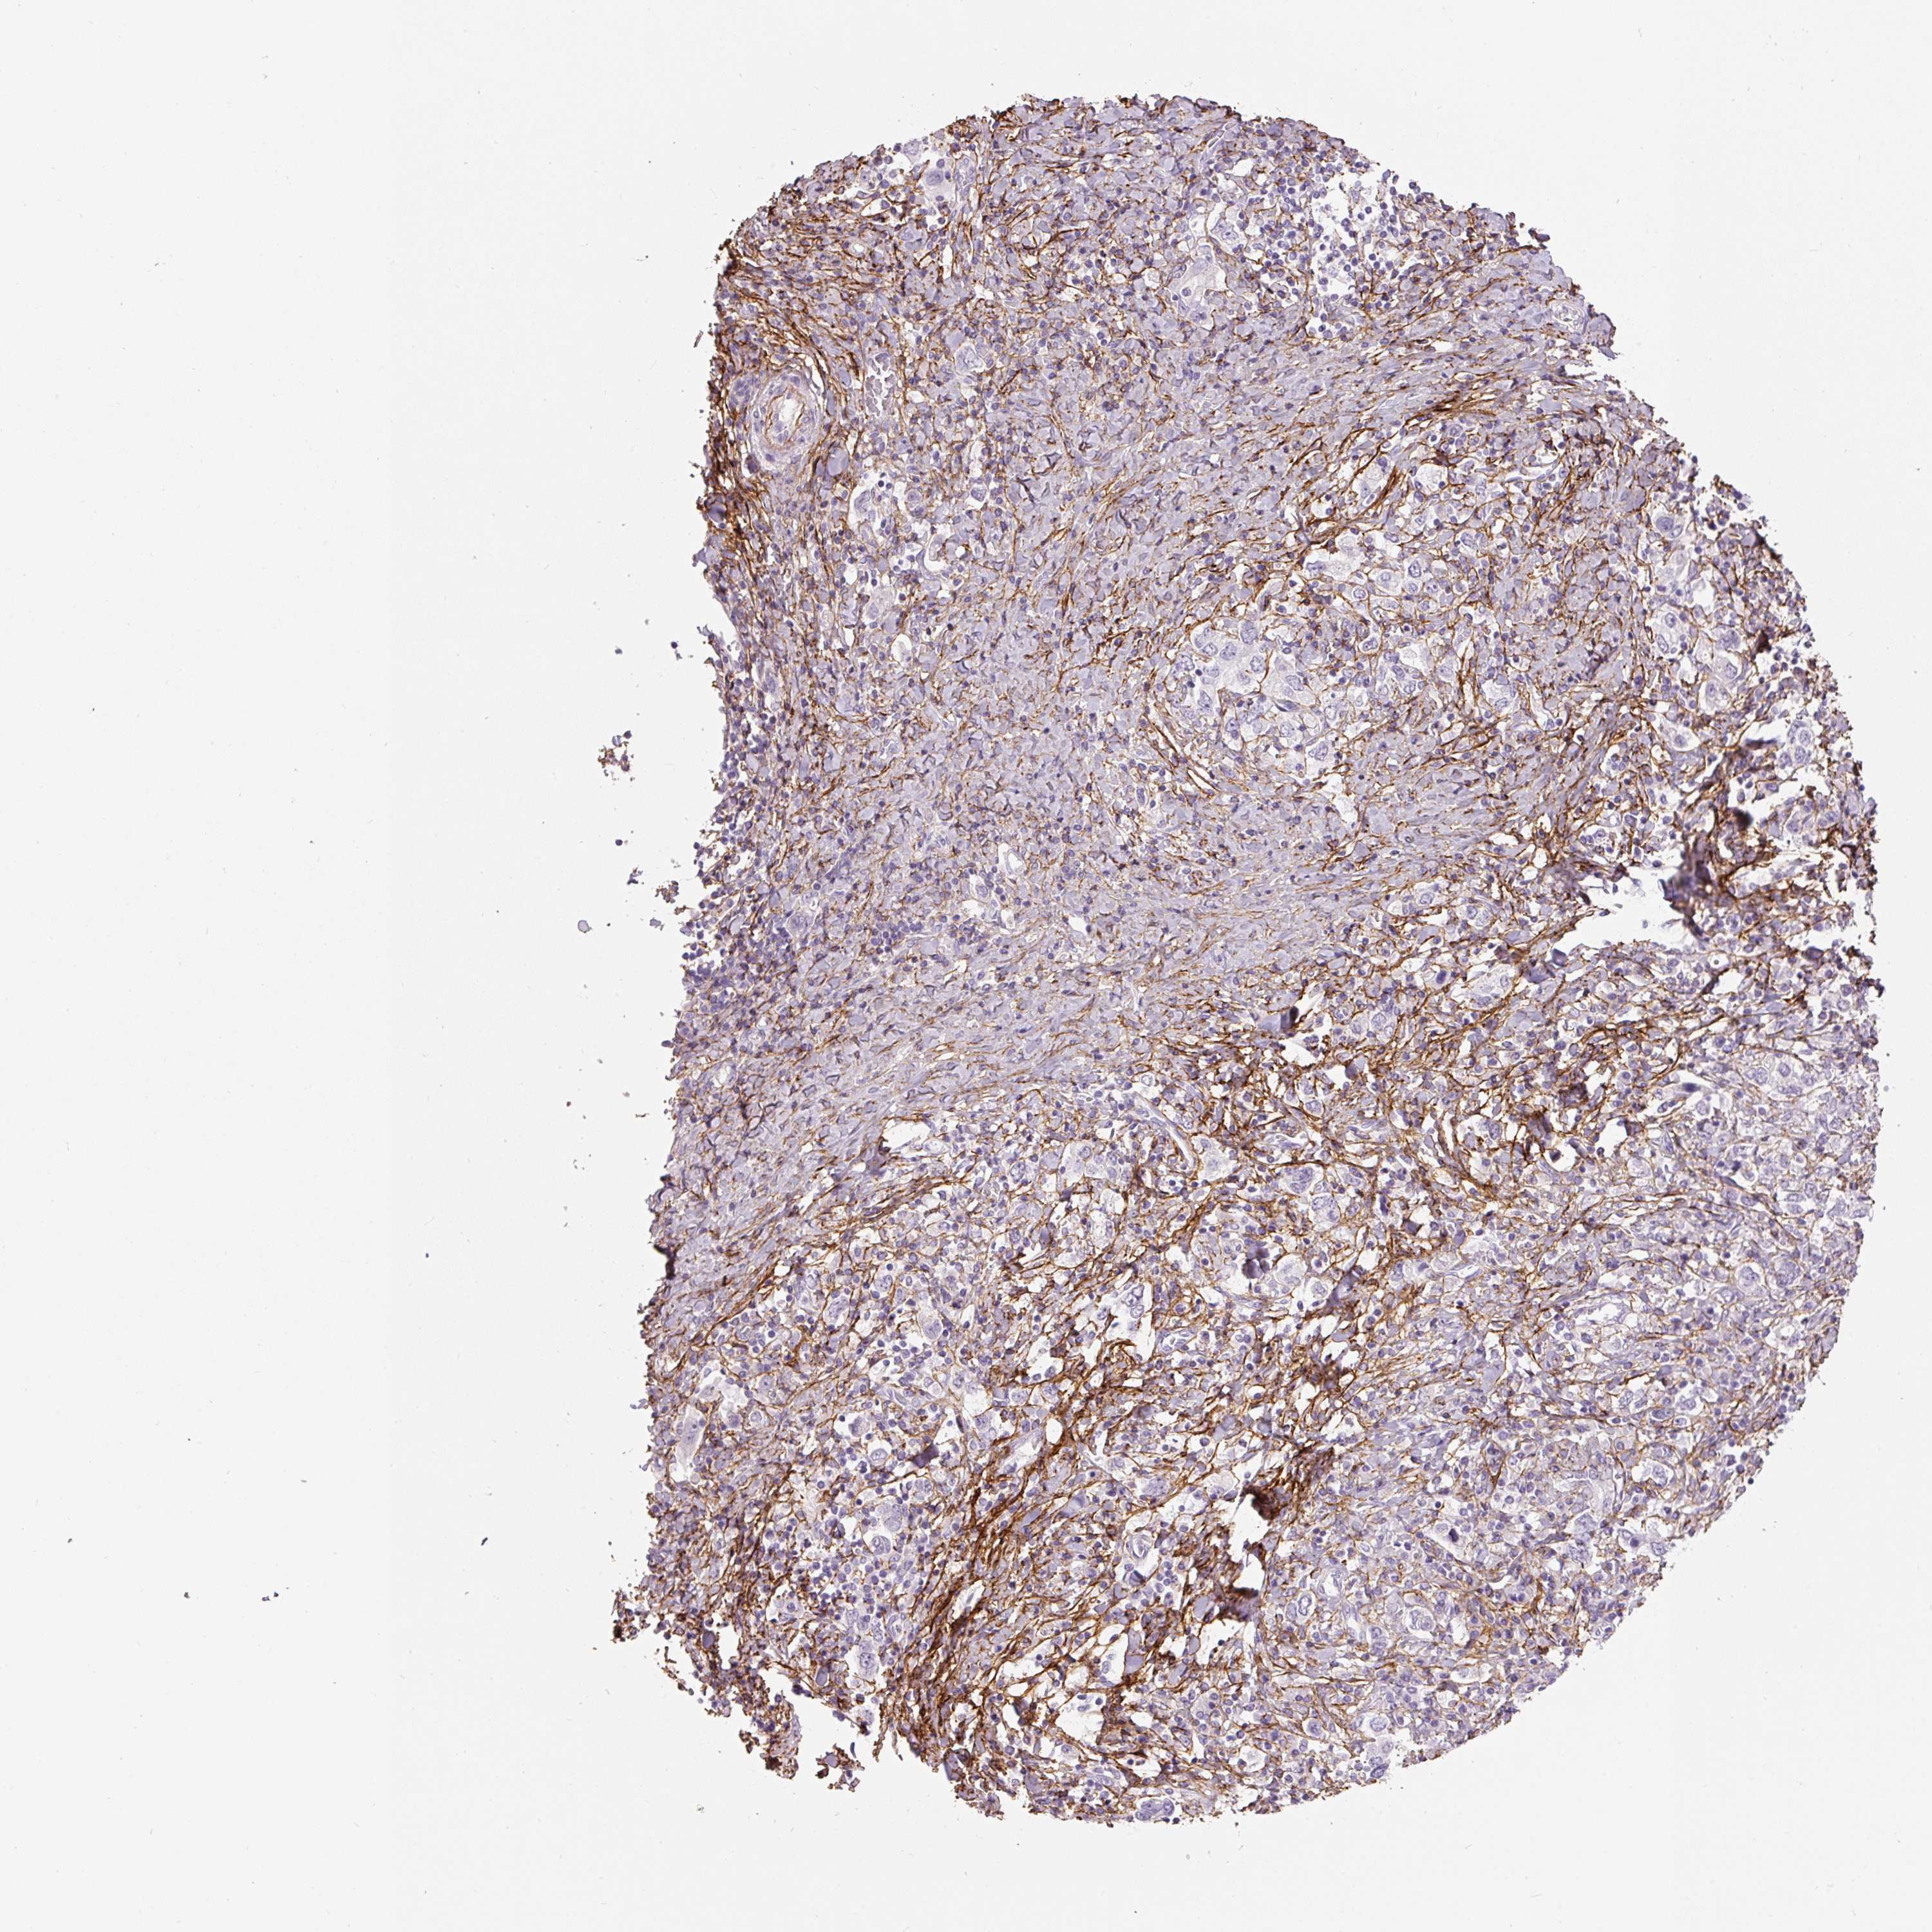

STOMACH CANCER - Protein expressioni

A mouse-over function shows sample information and annotation data. Click on an image to view it in a full screen mode. Samples can be filtered based on level of antibody staining by selecting one or several of the following categories: high, medium, low and not detected. The assay and annotation is described here.

Note that samples used for immunohistochemistry by the Human Protein Atlas do not correspond to samples in the TCGA dataset.

Antibody stainingi

Antibody staining in the annotated cell types in the current human tissue is reported as not detected, low, medium, or high, based on conventional immunohistochemistry profiling in selected tissues. This score is based on the combination of the staining intensity and fraction of stained cells.

Each image is clickable and will lead to virtual microscopy that enables deeper exploration of all samples and also displays staining intensity scores, fraction scores and subcellular localization as well as patient and tissue information for each sample.

HPA017759

HPA021057

CAB002670

CAB058696

CAB068188

CAB080202

Staining

High

Medium

Low

Not detected

Intensity

Strong

Moderate

Weak

Negative

Quantity

>75%

75%-25%

<25%

None

Location

Nuclear

Cytoplasmic/membranous

Cytoplasmic/membranous,nuclear

Adenocarcinoma, NOS

Adenocarcinoma, High grade